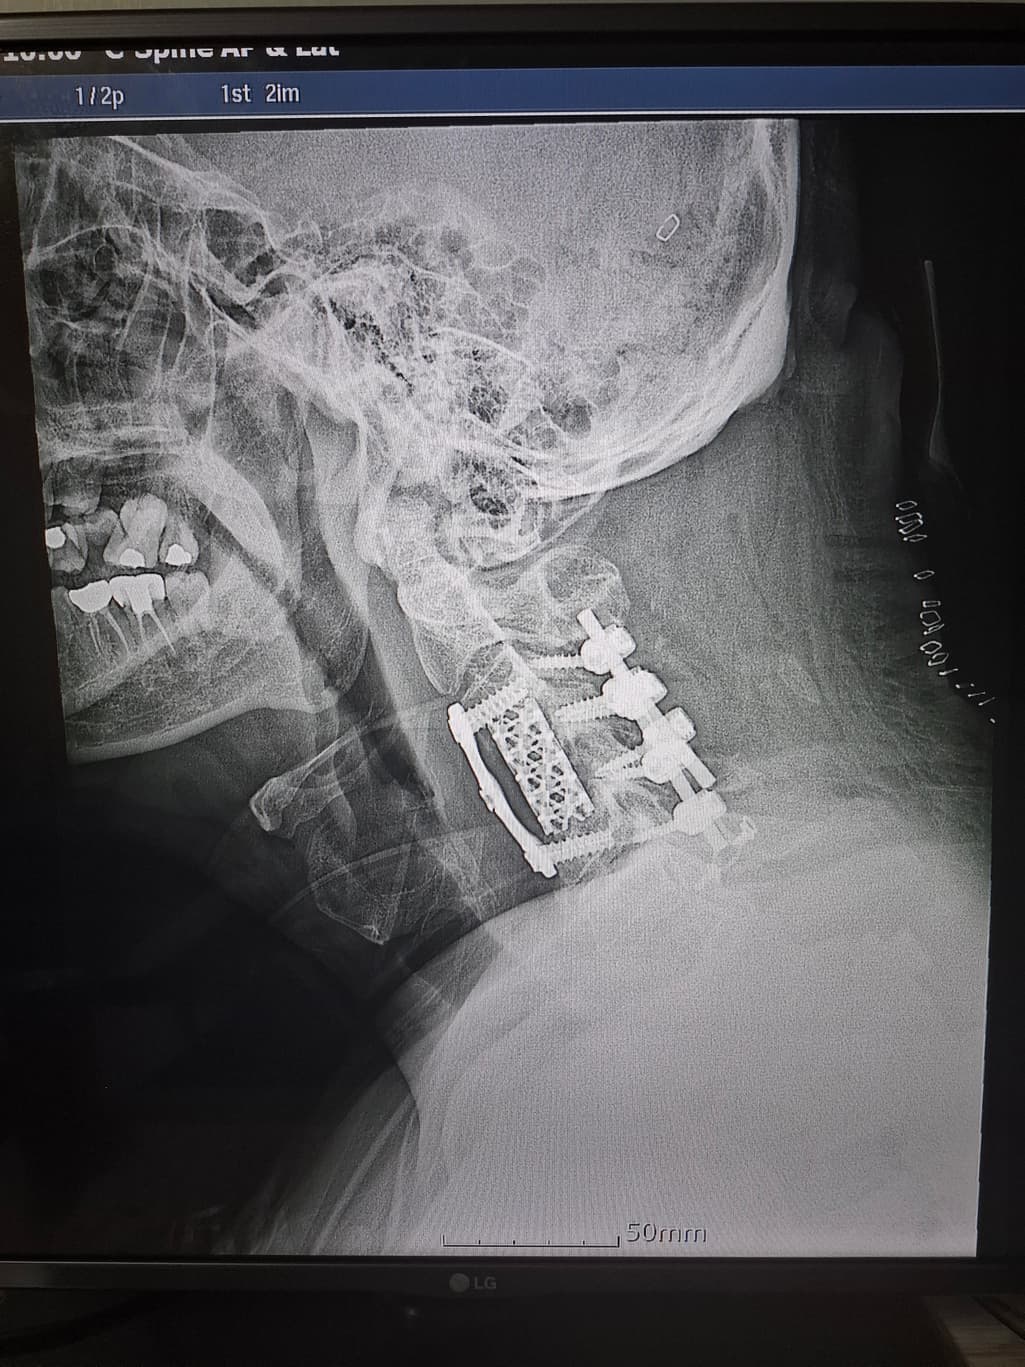

수술후 이런 상태인데요